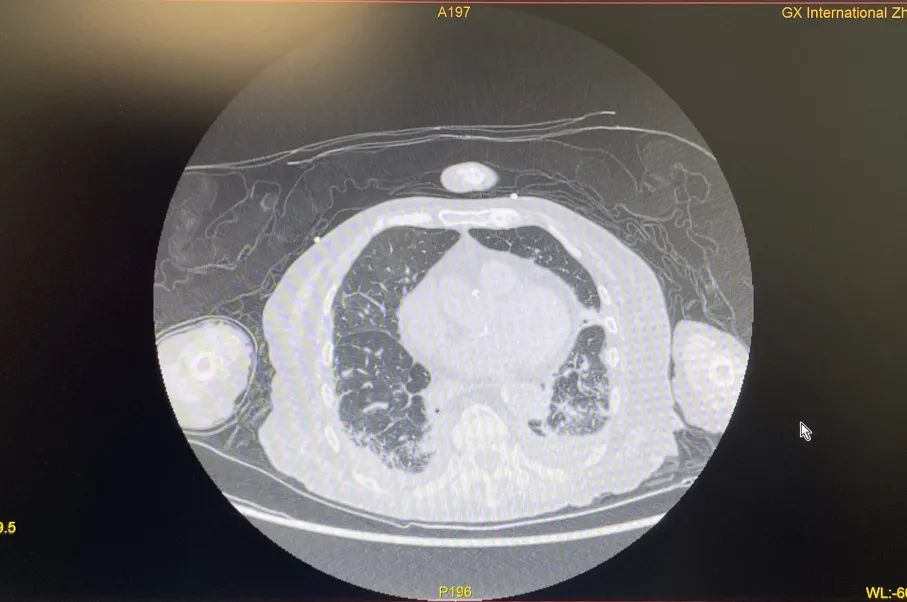

2022年12月末,87岁的胡奶奶因“气喘、咳嗽”等症状到国壮肾病科就医,被发现血氧低下和新型冠状病毒感染,经CT进一步检查发现其肺部感染严重。

胡奶奶肺炎程度高,氧合指数、氧分压极低。

治疗后,胡奶奶肺炎程度减轻,氧合指数、氧分压改善明显,脱离生命危险